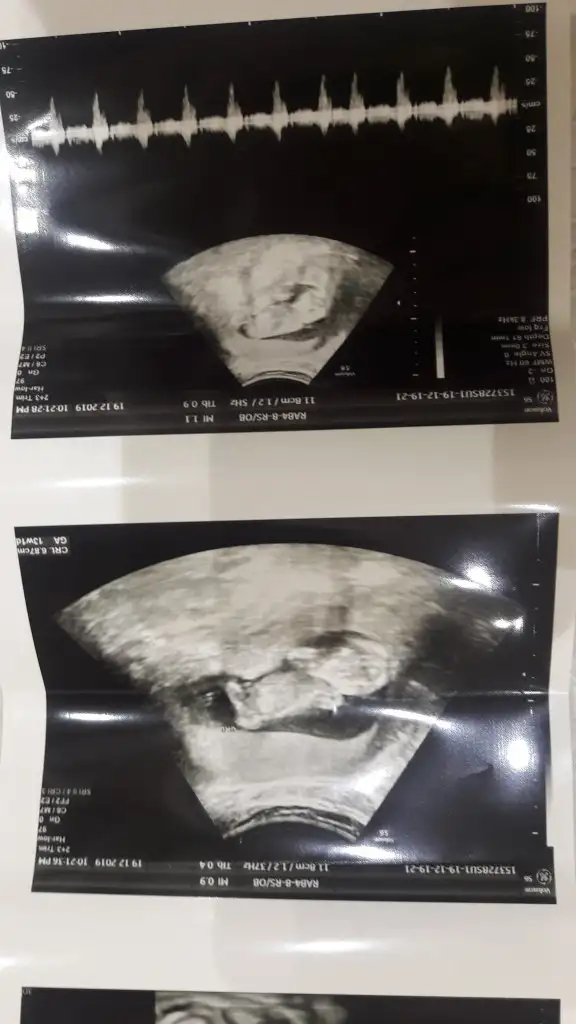

dr soylemeden siz gorun genital nub teorisi ( bebegin cinsiyeti)

Siz de yine bakarmısınız net söyledi kız diye herkes erkek demişti sizin gibi bende öyle diyordum ama ters köşe yaptı galiba bizimki çok hareketliydi 🤭🤣

ya kızlar bu resim bnim kaç gündür aklımı karstryo burda kız gibi doktor erkek dedi